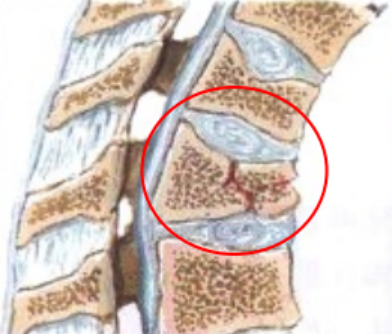

脊柱压缩性骨折,胸腰椎多见,骨折主要发生在胸或腰椎移行处,以 T12最多见,其次为L1。上位胸椎也可发生,颈椎骨折几乎没有。

C.压缩性骨折:椎体各部分高度均变小。其中最常见的是楔形压缩骨折(51%),常导致患者腰背痛、脊柱后凸畸形、呼吸功能降低等一系列并发症。